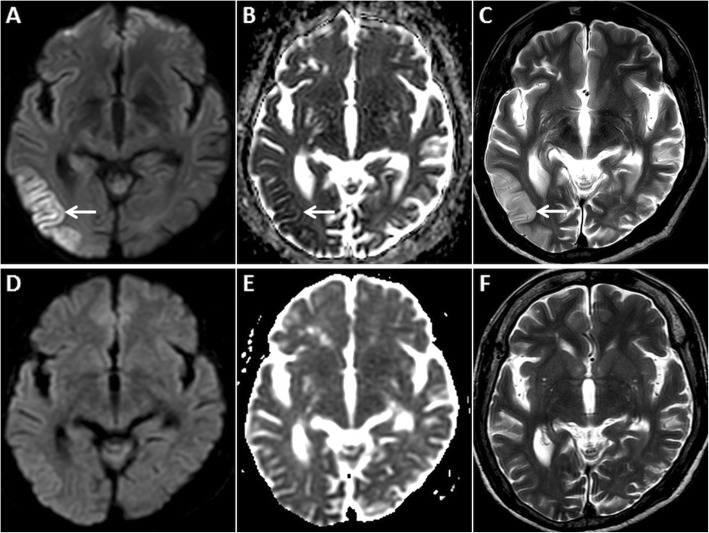

Fig. 3.

MRI of the brain in a 67-year-old female patient presenting with a seizure. GRD is observed in the right temporo-occipital region (arrow) on axial DWI (a) and ADC image (b). Also note associated cortical swelling and hyperintensity (arrow) on axial T2W image (c). Follow-up MRI after 4 days reveals complete resolution of the cortical signal abnormality and swelling on axial DWI, ADC and axial T2W images (d, e, f, respectively)

Fig 4.

MRI of the brain in a 68-year-old male patient presenting with severe hypoglycaemia. Extensive symmetric GRD (arrows) and restricted diffusion in deep white matter (arrowheads) is seen on axial DWI (a) and ADC image (b). Restricted diffusion is also seen in the putamina bilaterally (dashed arrow) on axial DWI (d) and ADC image (e). Axial FLAIR images (c, f) show hyperintense signal in the involved cortex (arrows) and in the putamina (dashed arrows)

Fig. 5.

MRI of the brain in a 46-year-old male patient diagnosed with hypoglycaemia on the background of diabetic ketoacidosis. Bilateral asymmetric GRD, more on the right, is seen in the temporo-occipital lobes (arrows) on axial DWI (a) and ADC image (b). Restricted diffusion is also seen in bilateral hippocampi (arrowheads). Mild hyperintensity is noted in the involved cortex (arrows) on the axial T2W image (c). Post-treatment follow-up MRI after 2 weeks shows partial resolution of signal changes on axial DWI and ADC images (d, e, respectively). Note that the axial T2W image also appears almost unremarkable (f)